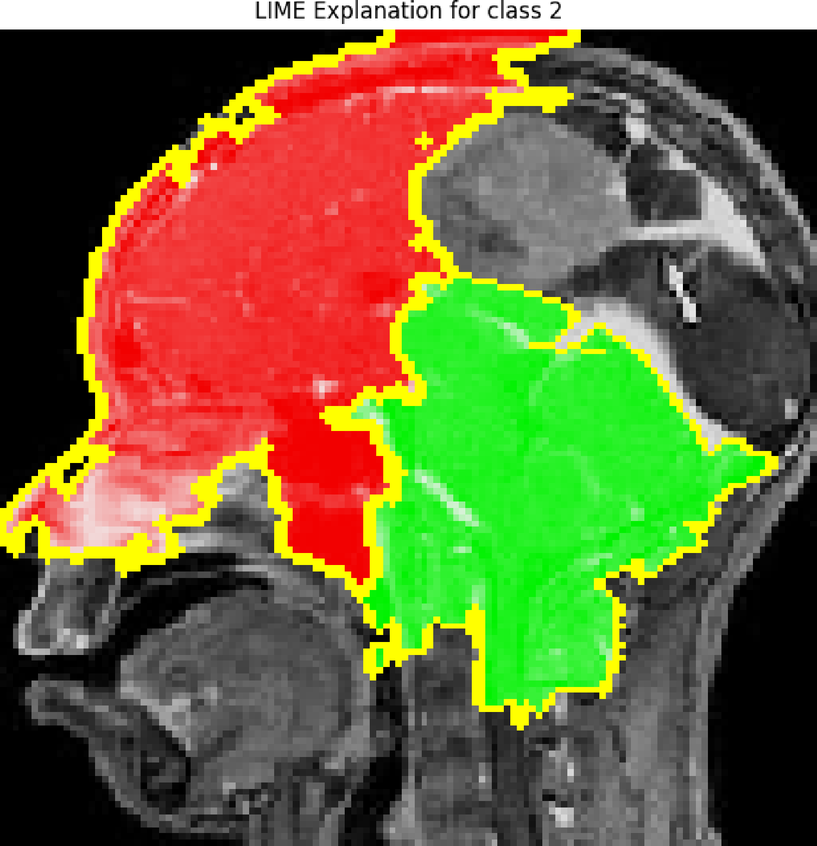

From: Advanced dynamic ensemble framework with explainability driven insights for precision brain tumor classification across datasets

LIMA XAI heatmap.